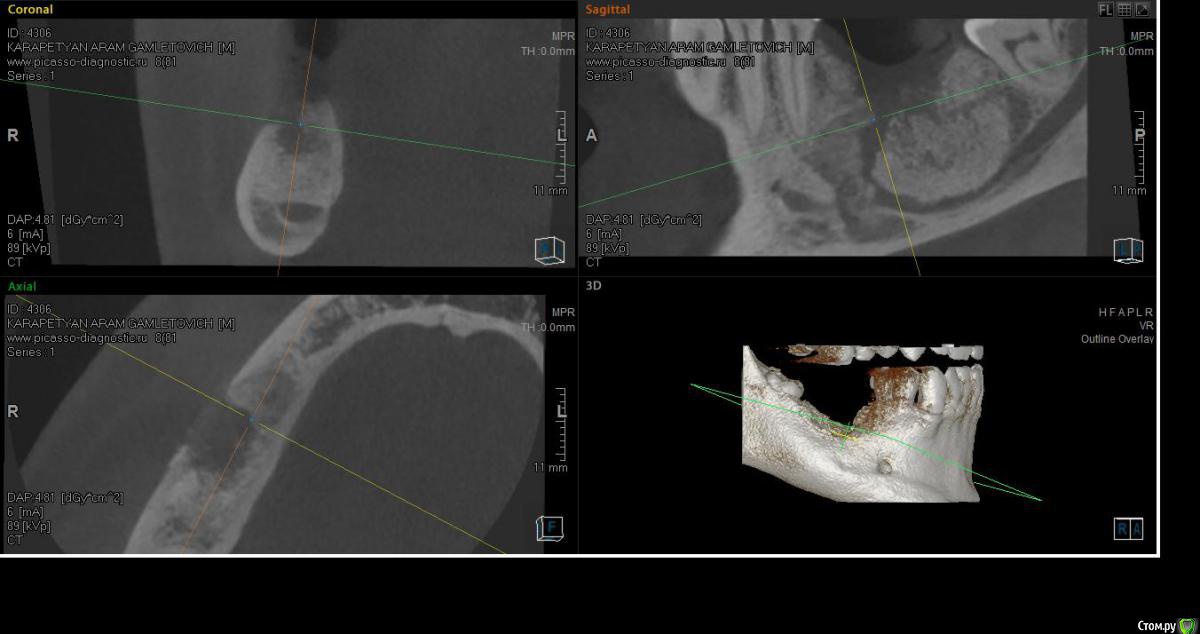

SashaDoc Опубликовано 14 сентября, 2015 Поделиться Опубликовано 14 сентября, 2015 (изменено) Коллеги, нужен совет. Со слов пациента, около 8 мес назад в Армении ему провели операцию по "удалению кисты" н/ч и "засыпали костный порошок" в объеме 6 гр. При мне пациент достал изо рта секвестр 10*5 мм, который он долгое время ощущал языком; во рту - небольшой (3*3мм) дефект слизистой, без отделяемого, в глубине зияет графт. Ничего не болит и не болело.На свежем кт картина не нравится, вопрос - что делать, куда направить? Пациент несколько в стомат теме и понимает, что что-то идет не так, тем более, что врач ему "обещал, что через пол года там кость будет" Изменено 14 сентября, 2015 пользователем SashaDoc Ссылка на комментарий